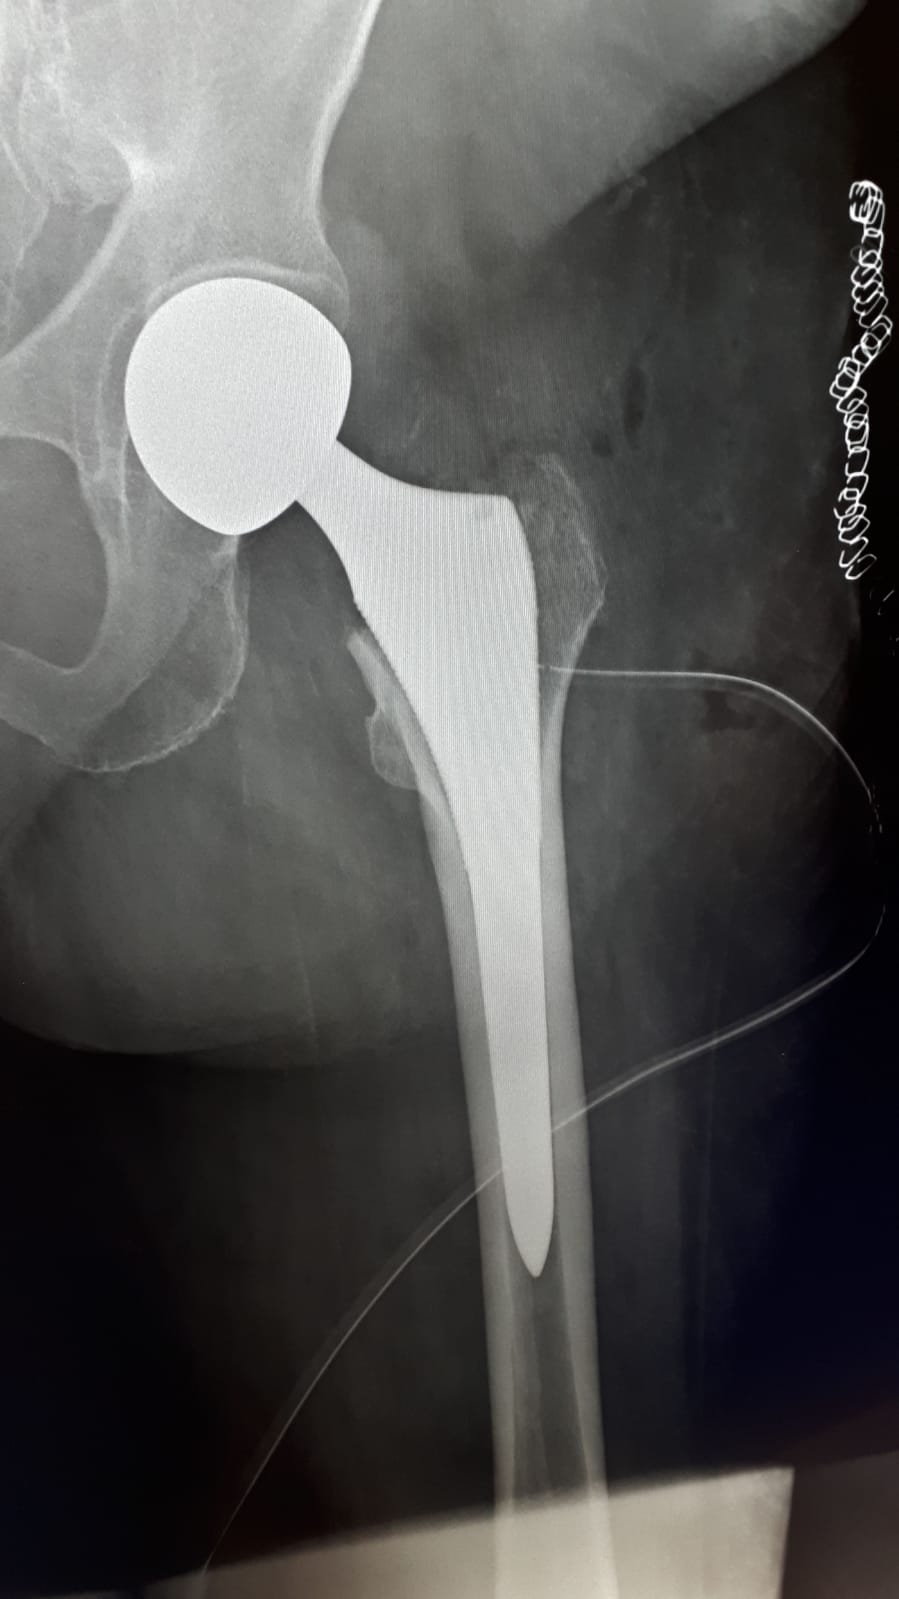

Si è svolto con ottimo esito, ieri 3 dicembre, un delicato intervento chirurgico di endoprotesi all’anca sinistra su paziente positiva al Covid, presso il Giannuzzi di Manduria.

Si tratta di una donna di 92 anni con diagnosi di frattura al collo del femore sinistro, risultata positiva al tampone oro-faringeo per Cov-Sars-2. La donna era stata accettata presso il Pronto Soccorso della struttura sanitaria Mater Dei di Bari il precedente 30 novembre: a causa di indisponibilità di posti letti in ASL Bari, la paziente è stata trasferita il giorno successivo presso il nosocomio di Manduria. L’intervento chirurgico, delicato per la positività al virus e l’età della paziente, si è svolto entro le 48 ore dal ricovero, come da protocollo. In tali casi, infatti, non è sempre possibile effettuare l’intervento chirurgico se la valutazione dei rischi è superiore ai benefici attesi.

Le fratture del femore e dell’anca si confermano come una priorità chirurgica anche in piena emergenza pandemica. L’intervento, guidato dal dr. Aldo Casto, direttore del reparto di Ortopedia e Traumatologia del presidio di Manduria, è stato eseguito grazie alla collaborazione sinergica tra medici anestesisti, cardiologi, gli operatori del reparto di Medicina Semi-intensiva e tutto il personale infermieristico e ausiliario.